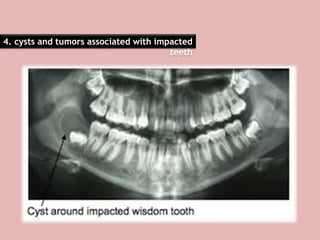

4. cysts and tumors associated with impacted

teeth

bone around the impacted teeth